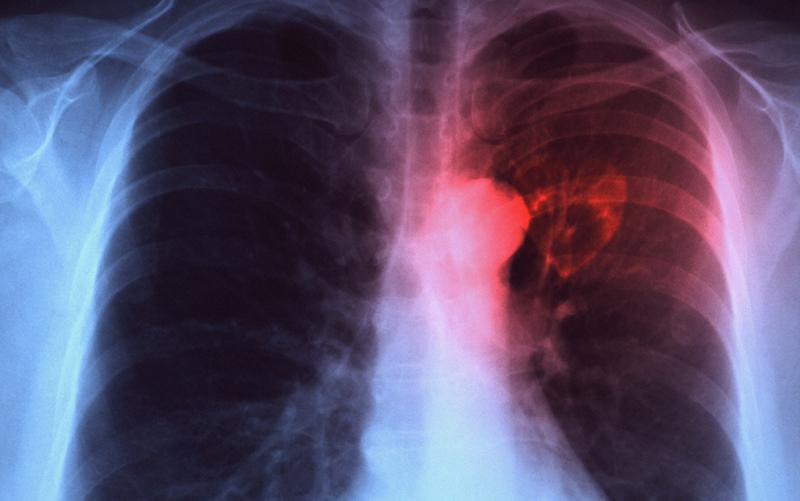

Contoh x ray pesakit tb. Sekiranya anda mengalami batuk berpanjangan doktor biasanya akan membuat sapuan kahak di bawah mikroskop untuk mengesan kuman tibi. Setelah dilakukan pengolahan ke 30 citra X-ray thorax tersebut terlihat bagian yang terkena kuman tuberkulosis terlihat lebih cerah dari citra aslinya dengan tingkat akurasi 8583. TB merupakan penyakit yang amat terkenal untuk muncul kemudian dalam hidup apabila orang itu menghidap penyakit kronik pada masa hadapan.

Hasil foto X-ray pada paru paru Anda nantinya akan menggambarkan dengan jelas bila Anda terkena TBC ini merupakan langkah awal dalam mendiagnosa penyakit TBC. X-ray pada dada juga boleh menunjukkan kerosakan yang mungkin berlaku pada paru-paru anda. Densitas foto lebih baik dibanding contoh 1 dan inspirasi lebih baik karena tampak hingga iga posterior nomor 10 namun rotasi kurang baik.

An x-ray image of the lungs used as an input for the processing of the image. Mereka yang menghidap penyakit kronik seperti diabetes tekanan darah tinggi buah pinggang 3. Penyakit ini disebabkan oleh kuman TB Tubercle Bacilli yang biasanya menjangkiti paru-paru.

CT scan Jika hasil X-ray kurang meyakinkan maka akan dilakukan proses CT scan untuk pencitraan lebih lanjut proses ini juga dilakukan jika ada dugaan TBC ini sudah menyebar ke oragn tubuh lainnya. Sebagai contoh penyakit ini boleh menjadi aktif apabila seseorang menjadi imunokompromi seperti dalam HIV atau penyakit kencing manis. Foto x-ray atau rongsen dada dilakukan untuk melihat kondisi paru-paru di sini juga dapat dibedakan apakah TBC sedang aktif atau tidak.

Ia disebarkan melalui udara apabila pesakit yang mempunyai kuman yang aktif batuk. One characteristic of pulmonary TB is attacked in the presence of spotting objects infiltrates in the lungs. Ujian x-ray dan kahak juga perlu dilakukan.

Sistem yang dirancang diverifikasi untuk 30 X-ray thorax penderita tuberkulosis. Pesakit TB Aktif yang menjalani rawatan rapi selama sekurang-kurangnya 2 minggu tidak lagi menyebarkan bakteria. Pulmonary TB disease is a chron ic disease that poses a health problem in the world including Indonesia.

Telah diketahui tb paru telah menjadi masalah kesehatan masayarakat yang signifikan di negara berkembang termasuk Indonesia. Tidak tampak diskontinuitas tulang. Terdapat presipitasi mycobakterium cavitas di apex tuberculosis paru kanan Mind Map Definisi Epidemiologi Klasifikasi Etiologi dan Faktor.

Dikenal dengan tes tuberkulin dilakukan dengan cara menyuntikkan zat ke dalam kulit lalu dilihat hasilnya oleh dokter setelah 3 hari. Selama ini paramedis mendiagnosis penderita TB tersebut hanya berdasarkan citra X-ray manual. Kes pertama TB di dunia dilihat pada jasad mumia paderi Nesperehen di Mesir.